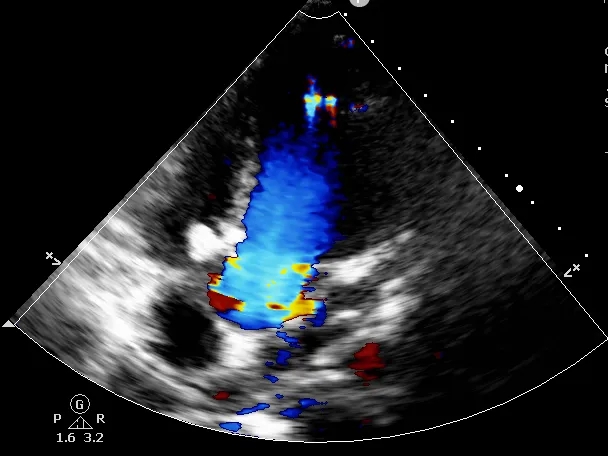

术前超声与DSA复测

VSD(膜周部):室间隔膜部瘤,左室面6.5mm,右室面呈“瘤样”结构,瘤体深度7mm,出口2mm。

该病灶呈现为“长隧道、大瘤底、小出口”的细腰形态,且位置紧邻主动脉瓣与三尖瓣,解剖结构较为复杂。此形态特征使得可降解封堵器在植入过程中的定位与释放面临较大挑战。

VSD(膜周部):左室面6.5mm,隔瓣下残缘5mm,基底形成5mm入口,右室面呈“瘤样”结构,出口孔2.5mm,三尖瓣隔瓣构成瘤壁的一部分。